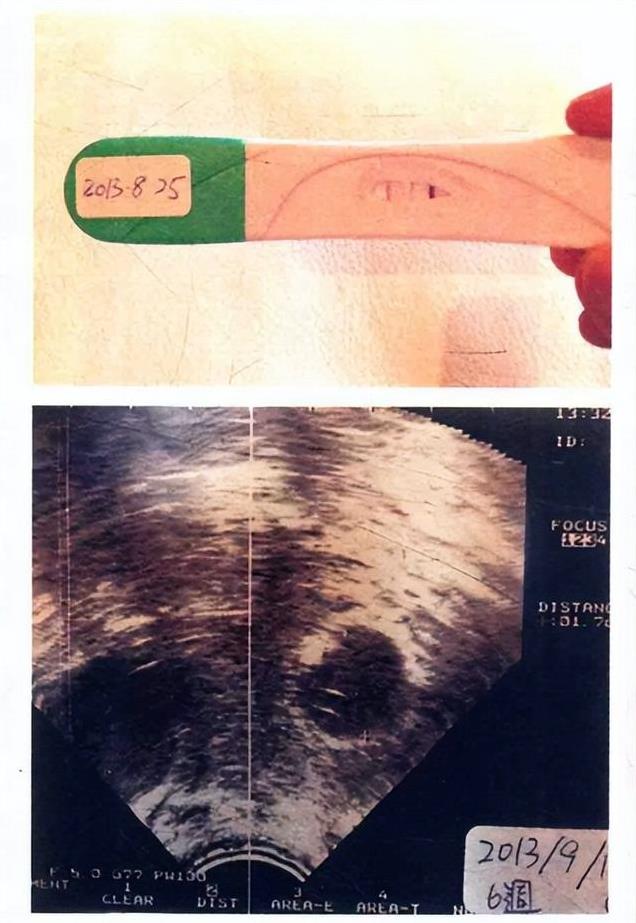

说到大S和汪小菲的婚姻,想当年那也是娱乐圈的一段佳话,一见钟情,浪漫邂逅,不知道羡煞了多少旁人。婚后,大S为了怀孕,那可是付出了巨大的努力,各种偏方,就为了孕育爱的结晶。她小心翼翼地守护着这个秘密,害怕失去,直到确认孩子平安,才告诉汪小菲,结果呢?换来的却只是一句冷冰冰的“嗯”。说实话,就这?就这?这简单的回应,或许早已暗示了这段婚姻的结局,真是让人扼腕叹息。